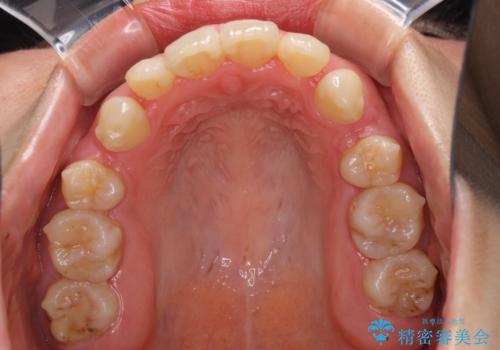

- 口元の突出感を気にして来院された患者様です。

診断の結果、上顎左右第一小臼歯4本抜歯により、叢生を解消するとともに口元を引っ込めていくことが望ましいと判断しました。

抜歯矯正による口元の改善にはワイヤー矯正が望ましいのですが、ダンサーとしての仕事を行っているため、インビザラインにて治療を行うこととしました。